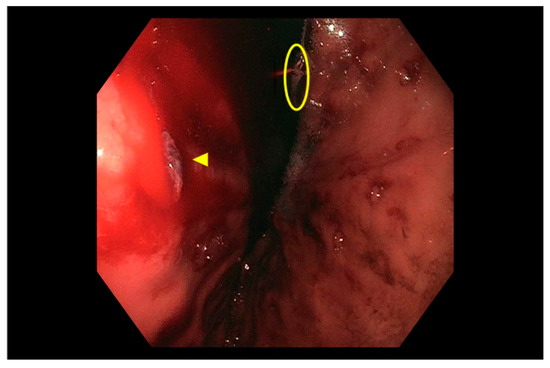

Jcm Free Full Text Diagnosis And Management Of Non Variceal